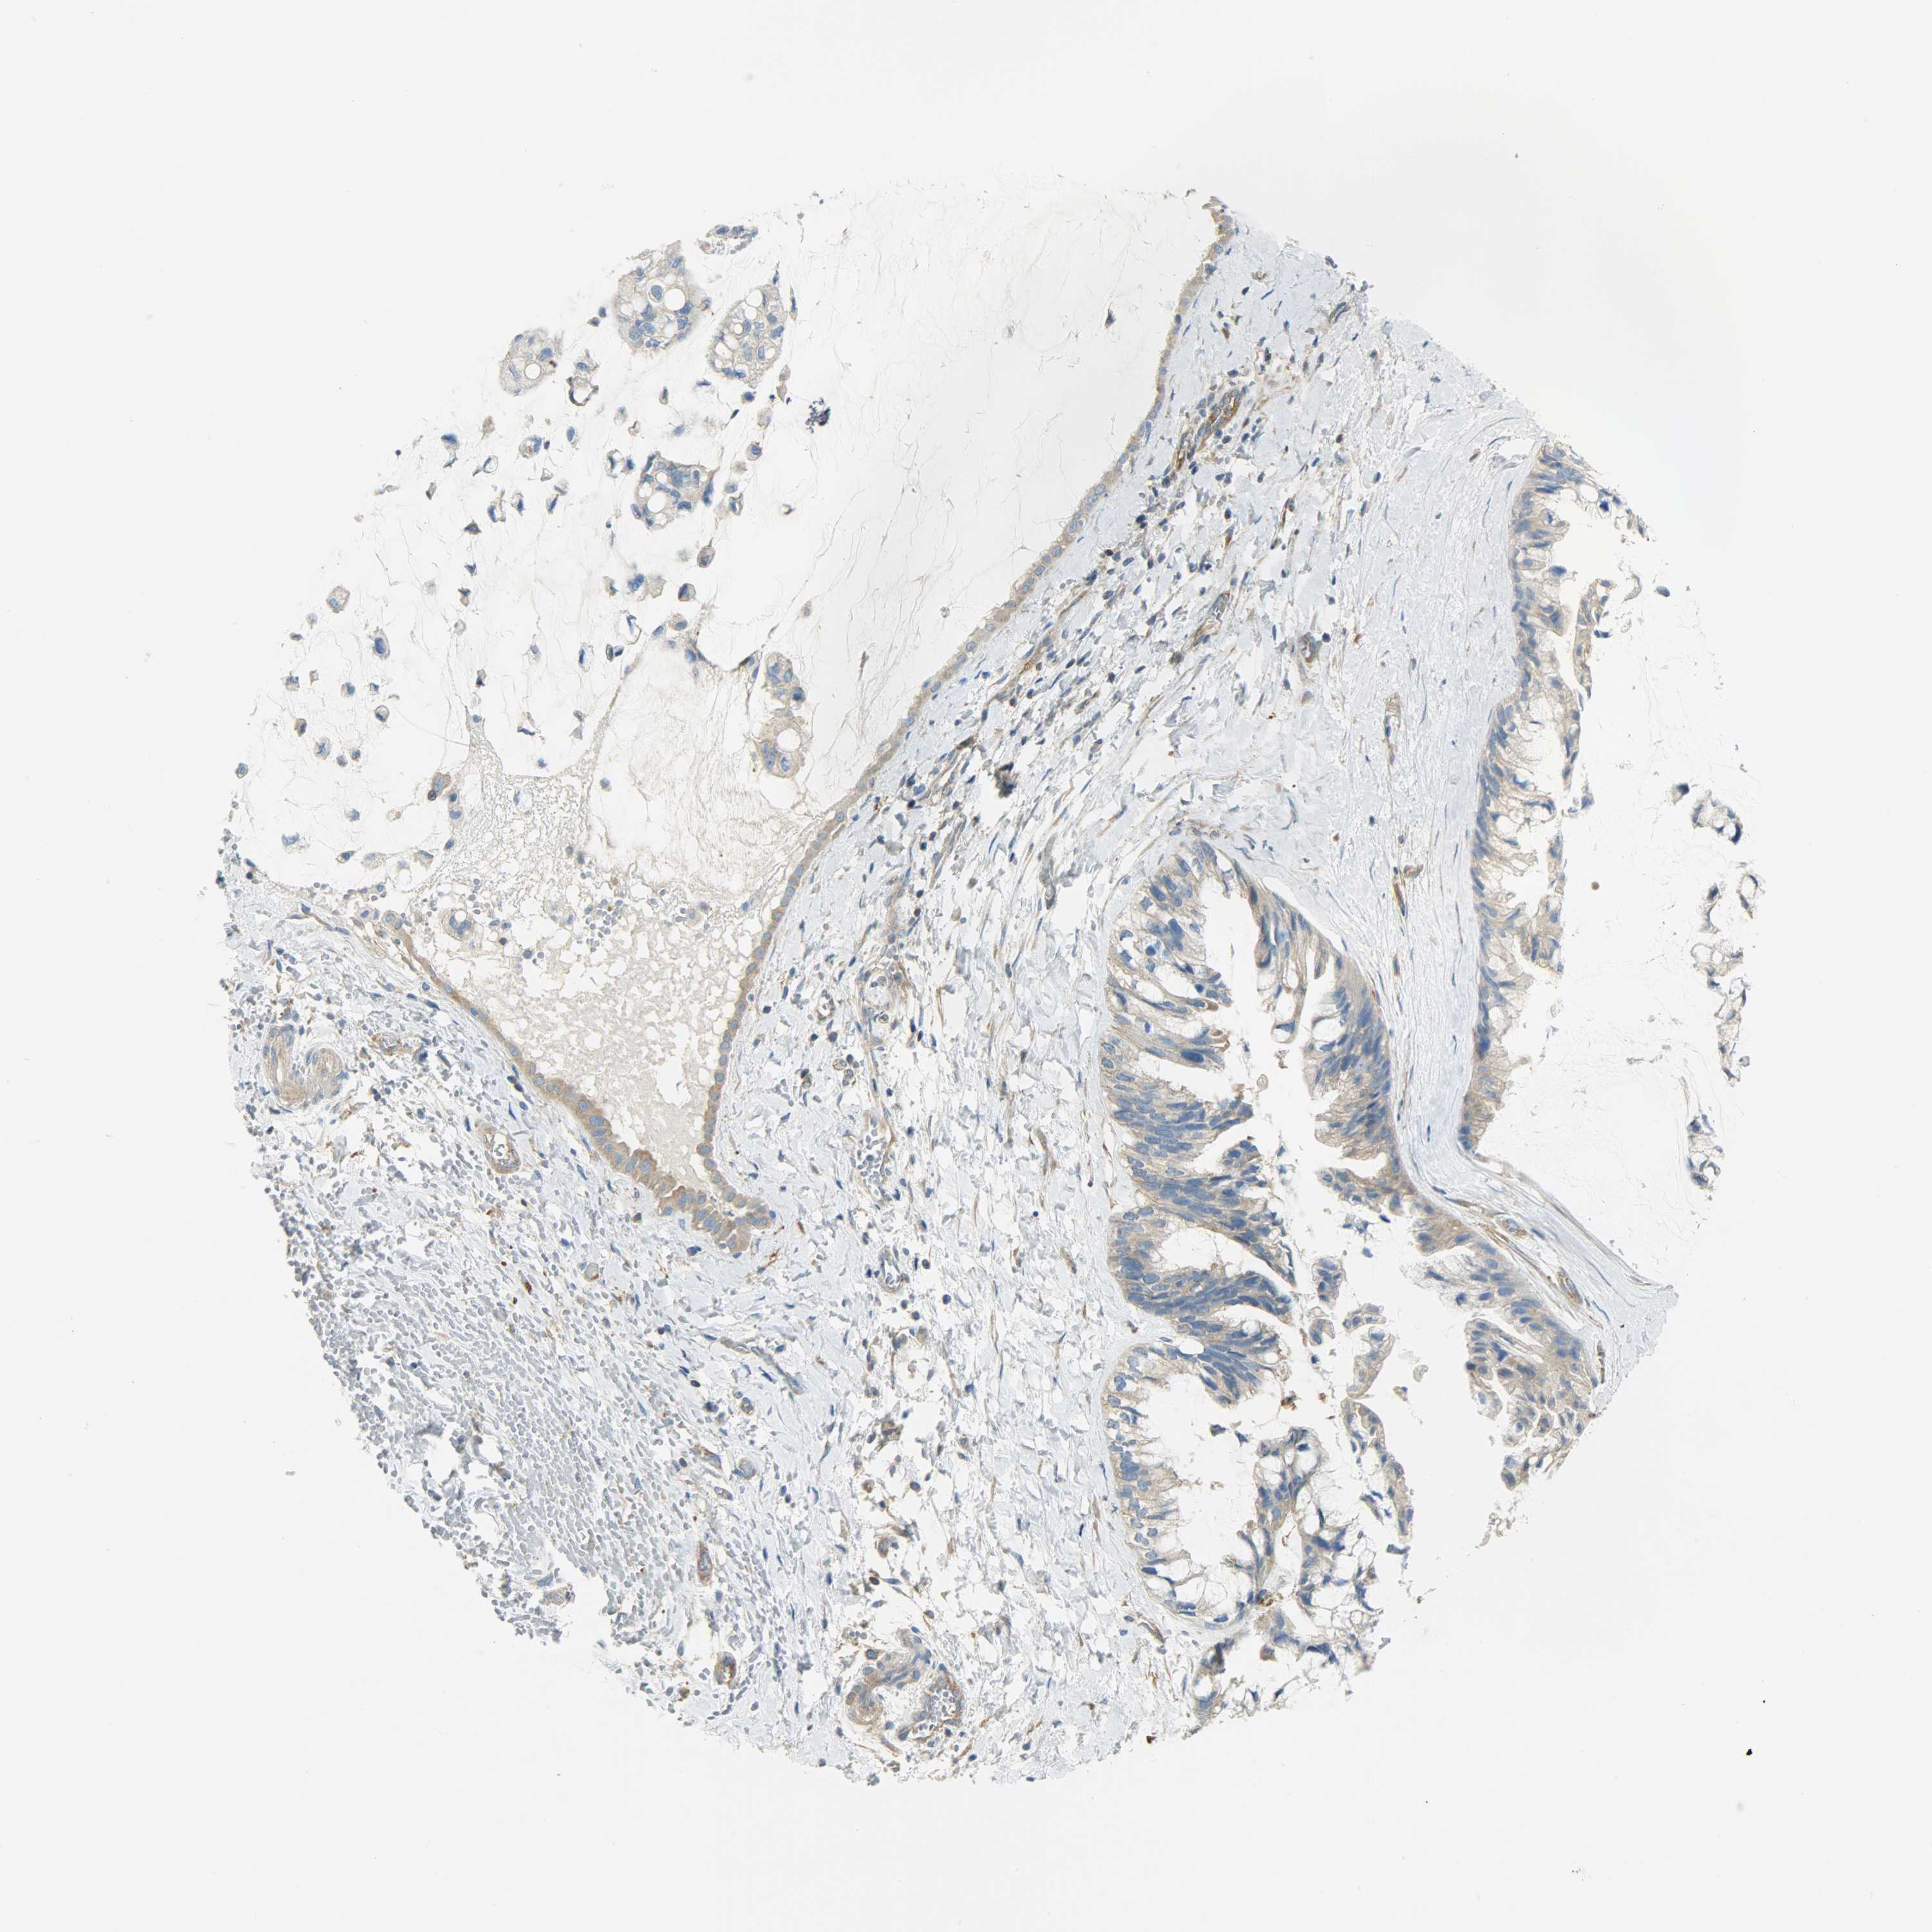

OVARIAN CANCER - Protein expressioni

A mouse-over function shows sample information and annotation data. Click on an image to view it in a full screen mode. Samples can be filtered based on level of antibody staining by selecting one or several of the following categories: high, medium, low and not detected. The assay and annotation is described here.

Note that samples used for immunohistochemistry by the Human Protein Atlas do not correspond to samples in the TCGA dataset.

Antibody stainingi

Antibody staining in the annotated cell types in the current human tissue is reported as not detected, low, medium, or high, based on conventional immunohistochemistry profiling in selected tissues. This score is based on the combination of the staining intensity and fraction of stained cells.

Each image is clickable and will lead to virtual microscopy that enables deeper exploration of all samples and also displays staining intensity scores, fraction scores and subcellular localization as well as patient and tissue information for each sample.

Antibody HPA004926

Staining

High

Medium

Low

Not detected

Intensity

Strong

Moderate

Weak

Negative

Quantity

>75%

75%-25%

<25%

None

Location

Nuclear

Cytoplasmic/membranous

Cytoplasmic/membranous,nuclear

Cystadenocarcinoma, serous, NOS

Carcinoma, endometroid

Carcinoma, NOS

Cystadenocarcinoma, mucinous, NOS